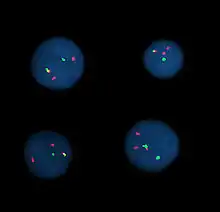

Hybridation in situ en fluorescence

La technique dite de FISH (Fluorescent In Situ Hybridization) est une technique qui permet de révéler par fluorescence grâce à des sondes d'ADN des séquences sur les chromosomes. Cela permet d'identifier des anomalies chromosomiques lors d'analyses pré- et post-natales. Chaque analyse ne permet d'identifier qu'une seule anomalie, et c'est une technique ciblée, les sondes utilisées ne sont pas choisies au hasard, mais font suite à de précédentes analyses (de biochimie en général).